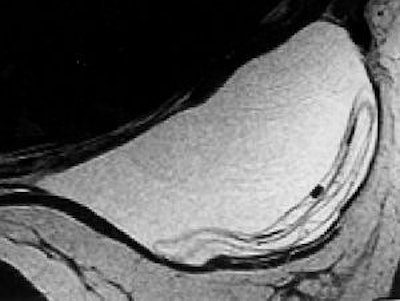

Ultrasound

Ultrasound can be used as a screening tool to detect implant rupture or leaks, but the sensitivity and specificity of ultrasound is lower than MRI. Of course, ultrasound is less expensive than MRI and has fewer patient limitations.

![]() |

| Sonogram of multiple discontinuous linear echoes (stepladder signs). Cursors denote anterior and posterior implant margins defined by fibrous capsule. Multiple parallel lines (arrows) represent floating envelope of this ruptured implant. Venta LS, CG Salomon CG, Flisa ME, Venta ER, Izquierdo R, Angelats J, "Sonographic signs of breast implant rupture" (AJR, 1996;166:1413-1419). |